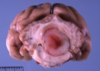

Name & describe the pathologic process.

Porencephaly

Cystic cavitation of the brain, usually involving cerebral white matter